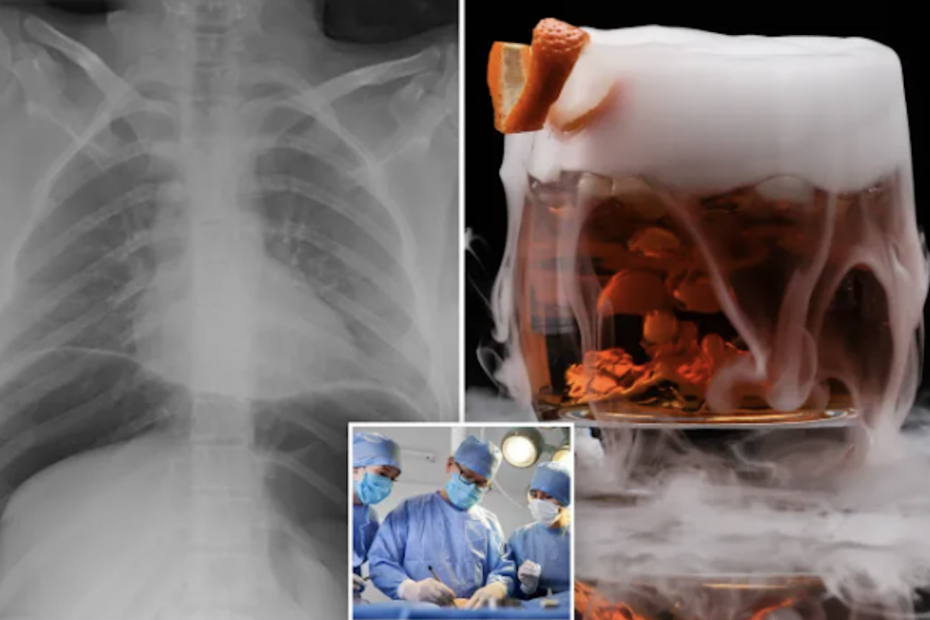

Cocktailurile care „fumegă” au devenit un simbol al barurilor exclusiviste și al mixologiei moderne. Arată bine în poze. Creează efect. Pot însă provoca leziuni grave, chiar fatale. Medicii avertizează că ingredientul responsabil pentru acest spectacol vizual, azotul lichid, poate transforma o seară banală într-o urgență chirurgicală.

În interiorul stomacului, această expansiune violentă poate duce la perforație. Practic, stomacul se poate rupe. Gazul eliberat umflă abdomenul, comprimă organele interne și poate provoca insuficiență respiratorie. În paralel, frigul extrem poate distruge țesuturile.

Fără intervenție chirurgicală imediată, riscul de deces este real.

Imediat după ingestie, a acuzat dureri abdominale intense și dificultăți de respirație. Investigațiile imagistice au arătat o perforație de stomac. Medicii au fost nevoiți să intervină chirurgical de urgență.

Din cauza țesutului necrotic din jurul leziunii, stomacul nu a putut fi reparat. Chirurgii au efectuat o gastrectomie, îndepărtând o porțiune din stomac și reconectând tractul digestiv la esofag.